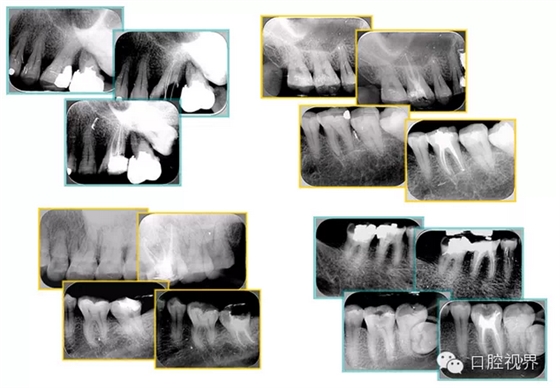

共有 4 張 X 線片,分別是術(shù)前、診斷絲 、主牙膠尖確認、術(shù)后。

( 1 )術(shù)前:術(shù)前 X 線片用來了解牙齒的大概情況。術(shù)前預(yù)期為多根牙時 X 線片應(yīng)偏頭拍攝。

( 2 )診斷絲:根據(jù)術(shù)前 X 線片進行開髓、根管的初步預(yù)備后,需要插入診斷絲,用來指示工作器械位置。常用 10 號或 15 號擴大器作為診斷絲插入牙髓腔。

( 3 )主牙膠尖確認:通過術(shù)前預(yù)期和診斷絲診斷,明確工作長度、牙根走向,進行根管預(yù)備。之后應(yīng)進行主牙膠尖(中銼)確認,已明確根管是否適合充填。

( 4 )術(shù)后:觀察治療效果。